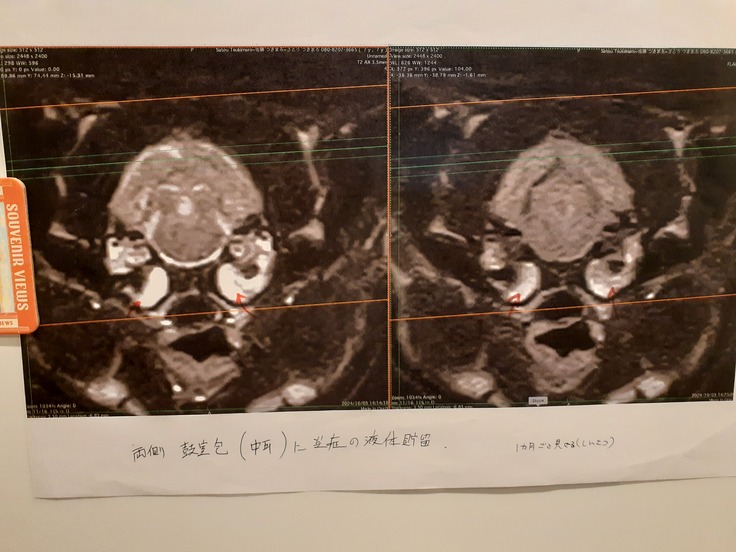

愛護センターから9月19日にお迎えしています。職員もなにかが変という認識があり、ねこ活にきました。立っていられずすぐ転がるということ、排尿排便はそこら辺にしてしまい、そのまま寝てしまう。そんな話を聞き、センターの帰り道に病院に行き、麻痺や、変形性関節症と言われましたが今までの経験からそれではない何か。を疑い、6日後に別の病院へ。脳に何か異常があるのではないかと検査を進められ、検査ができる系列病院にてX検査、MRI検査、神経学検査、便検査をしました。

結果としては大脳低形成という脳の発育不良が分かり、MRI検査をしたことで運良く中耳炎が見つかりました。

現在は抗生剤を3か月継続、1月18日にCTをして結果次第では投薬終了、または管を通した排膿をする予定になっています。